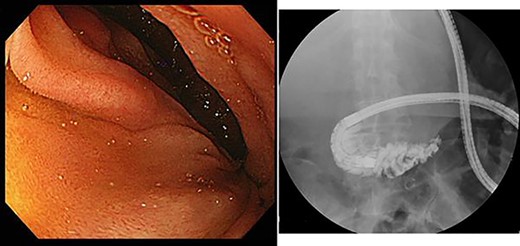

Upper gastrointestinal endoscopy showed severe duodenal stenosis due to compression from outside of the wall, which was the cause of gastric pain and anorexia (Fig. 3).

Upper gastrointestinal endoscopy showed severe stenosis of the duodenum.